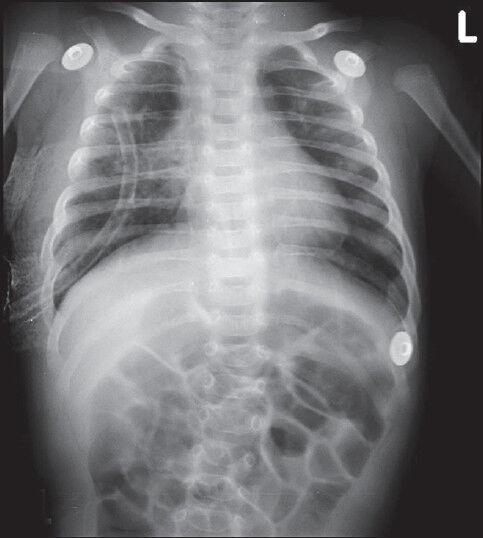

Congenital lobar emphysema (CLE) is a rare congenital anomaly of lung causing over aeration of one or more lobes of a histologically normal lung. It presents in infancy with respiratory distress due to compression atelectasis and often associated with mediastinal shift and hypotension. CLE poses a challenge in diagnosis and positive pressure ventilation due to air trapping. We report a case of 8-week-old infant with CLE posted for right lobectomy. Strategies to prevent misdiagnosis, over aeration and use of IPPV have been reviewed.

先天性肺叶气肿(CLE)是一种罕见的先天性肺部异常,可导致组织学正常的一个或多个肺叶过度充气。它在婴儿期因压迫性肺不张而出现呼吸窘迫,常伴有纵隔移位和低血压。由于气体潴留,CLE在诊断和正压通气方面构成挑战。我们报告一例8周大患有CLE的婴儿拟行右肺叶切除术。已对预防误诊、过度充气和使用间歇正压通气的策略进行了综述。